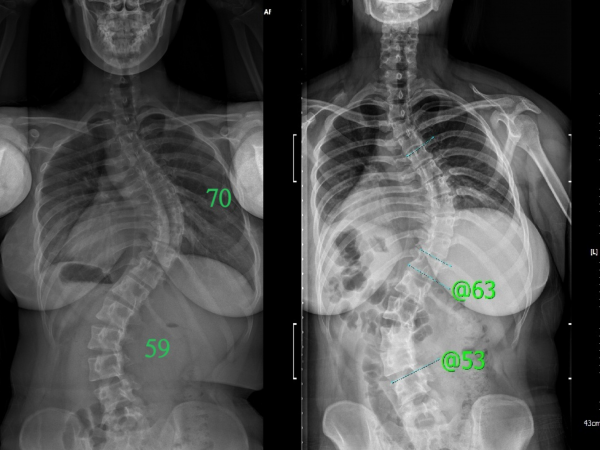

교정사례

PHS효과?